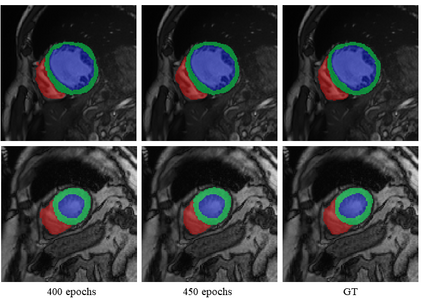

Multi-sequence cardiac magnetic resonance (CMR) provides essential pathology information (scar and edema) to diagnose myocardial infarction. However, automatic pathology segmentation can be challenging due to the difficulty of effectively exploring the underlying information from the multi-sequence CMR data. This paper aims to tackle the scar and edema segmentation from multi-sequence CMR with a novel auto-weighted supervision framework, where the interactions among different supervised layers are explored under a task-specific objective using reinforcement learning. Furthermore, we design a coarse-to-fine framework to boost the small myocardial pathology region segmentation with shape prior knowledge. The coarse segmentation model identifies the left ventricle myocardial structure as a shape prior, while the fine segmentation model integrates a pixel-wise attention strategy with an auto-weighted supervision model to learn and extract salient pathological structures from the multi-sequence CMR data. Extensive experimental results on a publicly available dataset from Myocardial pathology segmentation combining multi-sequence CMR (MyoPS 2020) demonstrate our method can achieve promising performance compared with other state-of-the-art methods. Our method is promising in advancing the myocardial pathology assessment on multi-sequence CMR data. To motivate the community, we have made our code publicly available via https://github.com/soleilssss/AWSnet/tree/master.